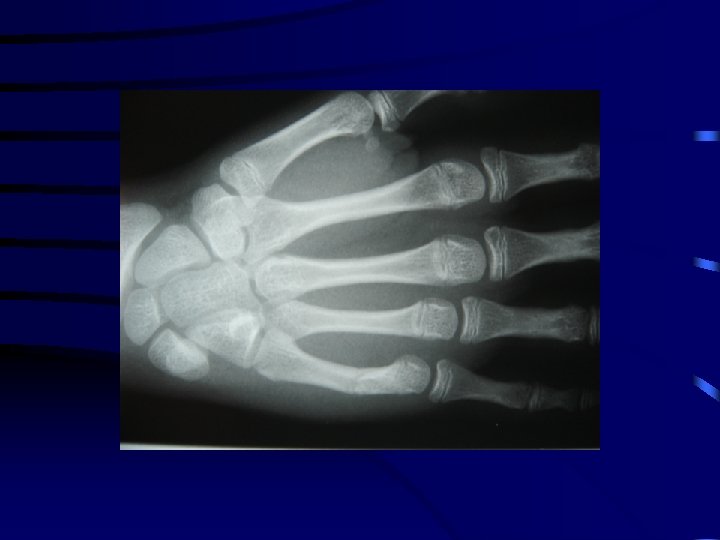

2 La fracture en bois vert • Il s'agit d'une fracture uni corticale : • Il est le plus souvent nécessaire de réduire ces fractures sous anesthésie. • La réduction nécessitera une rupture de la corticale non rompue pour éviter le déplacement secondaire sous plâtre.

3 La fracture en motte de beurre • Il s'agit d'un tassement métaphysaire par impaction de la diaphyse dans la métaphyse. • L'exemple le plus fréquent est celui de la métaphyse inférieure du radius. • Il n'y a pas de risque de déplacement secondaire et une simple immobilisation antalgique est généralement nécessaire.

La fracture en motte de beurre